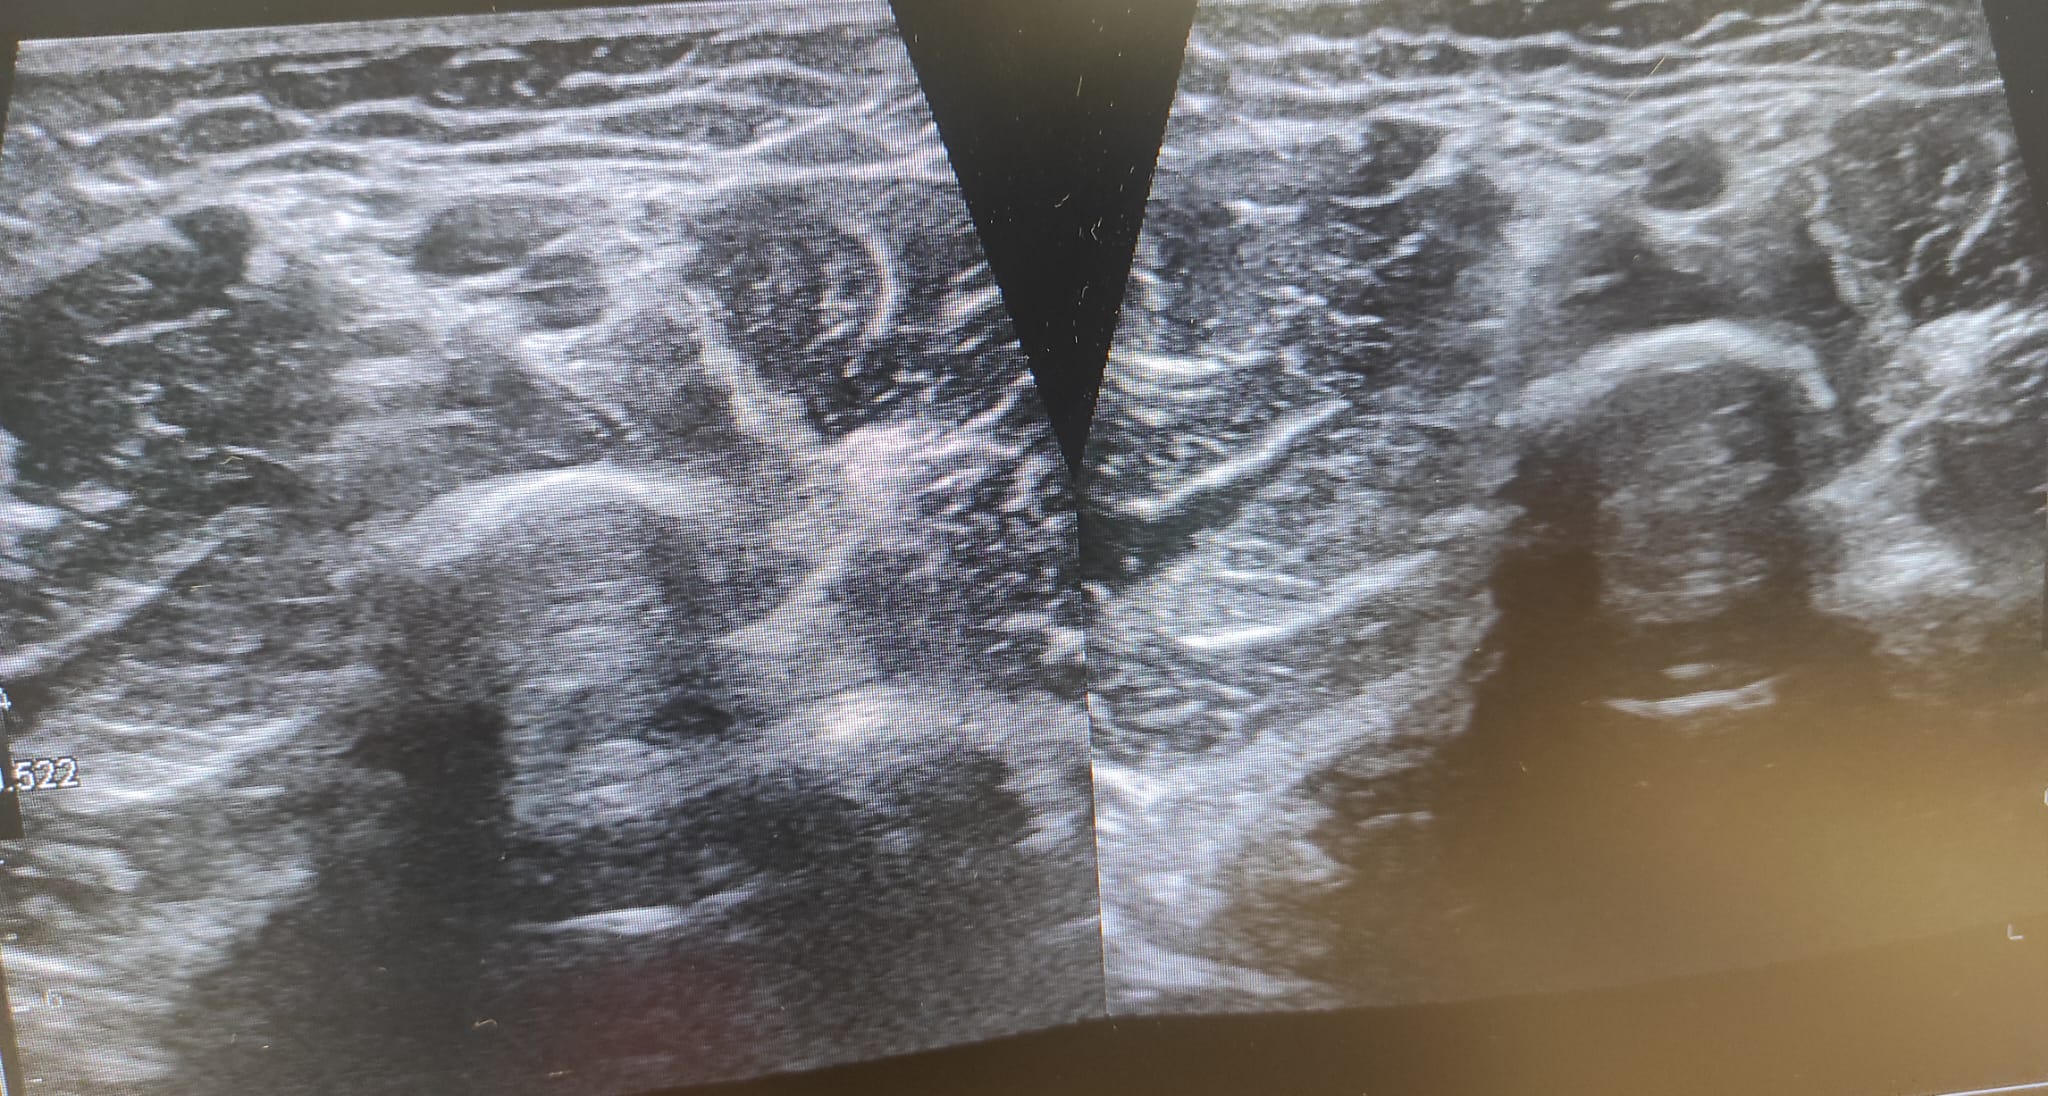

Ecografía doppler: Vena cefálica desde codo hasta distal ocupada por material ecogénico intraluminal, ausencia de flujo y falta de compresibilidad, compatible con trombosis venosa superficial. Resto de estudio venoso sin datos de trombosis.

Diagnóstico principal: Trombosis venosa superficial de miembro superior izquierdo.